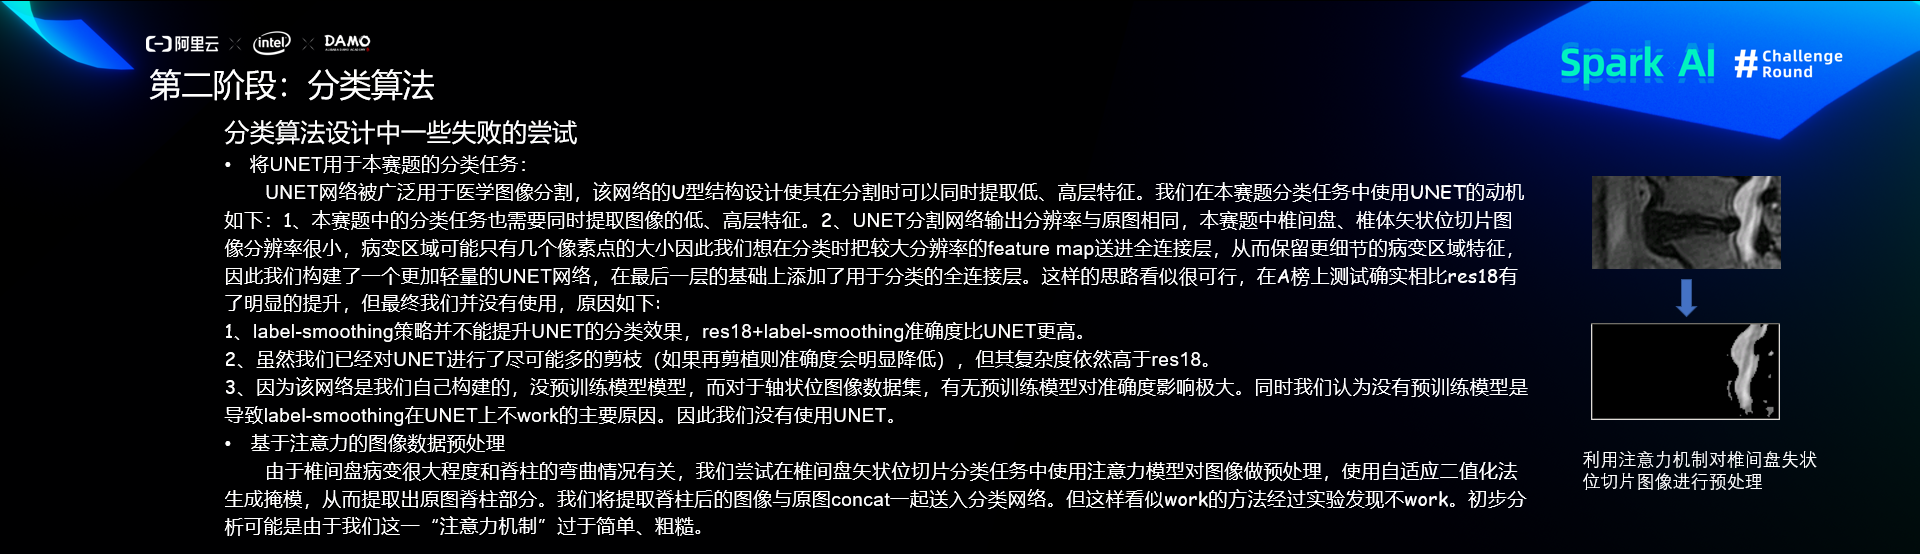

第二阶段:分类

分类算法